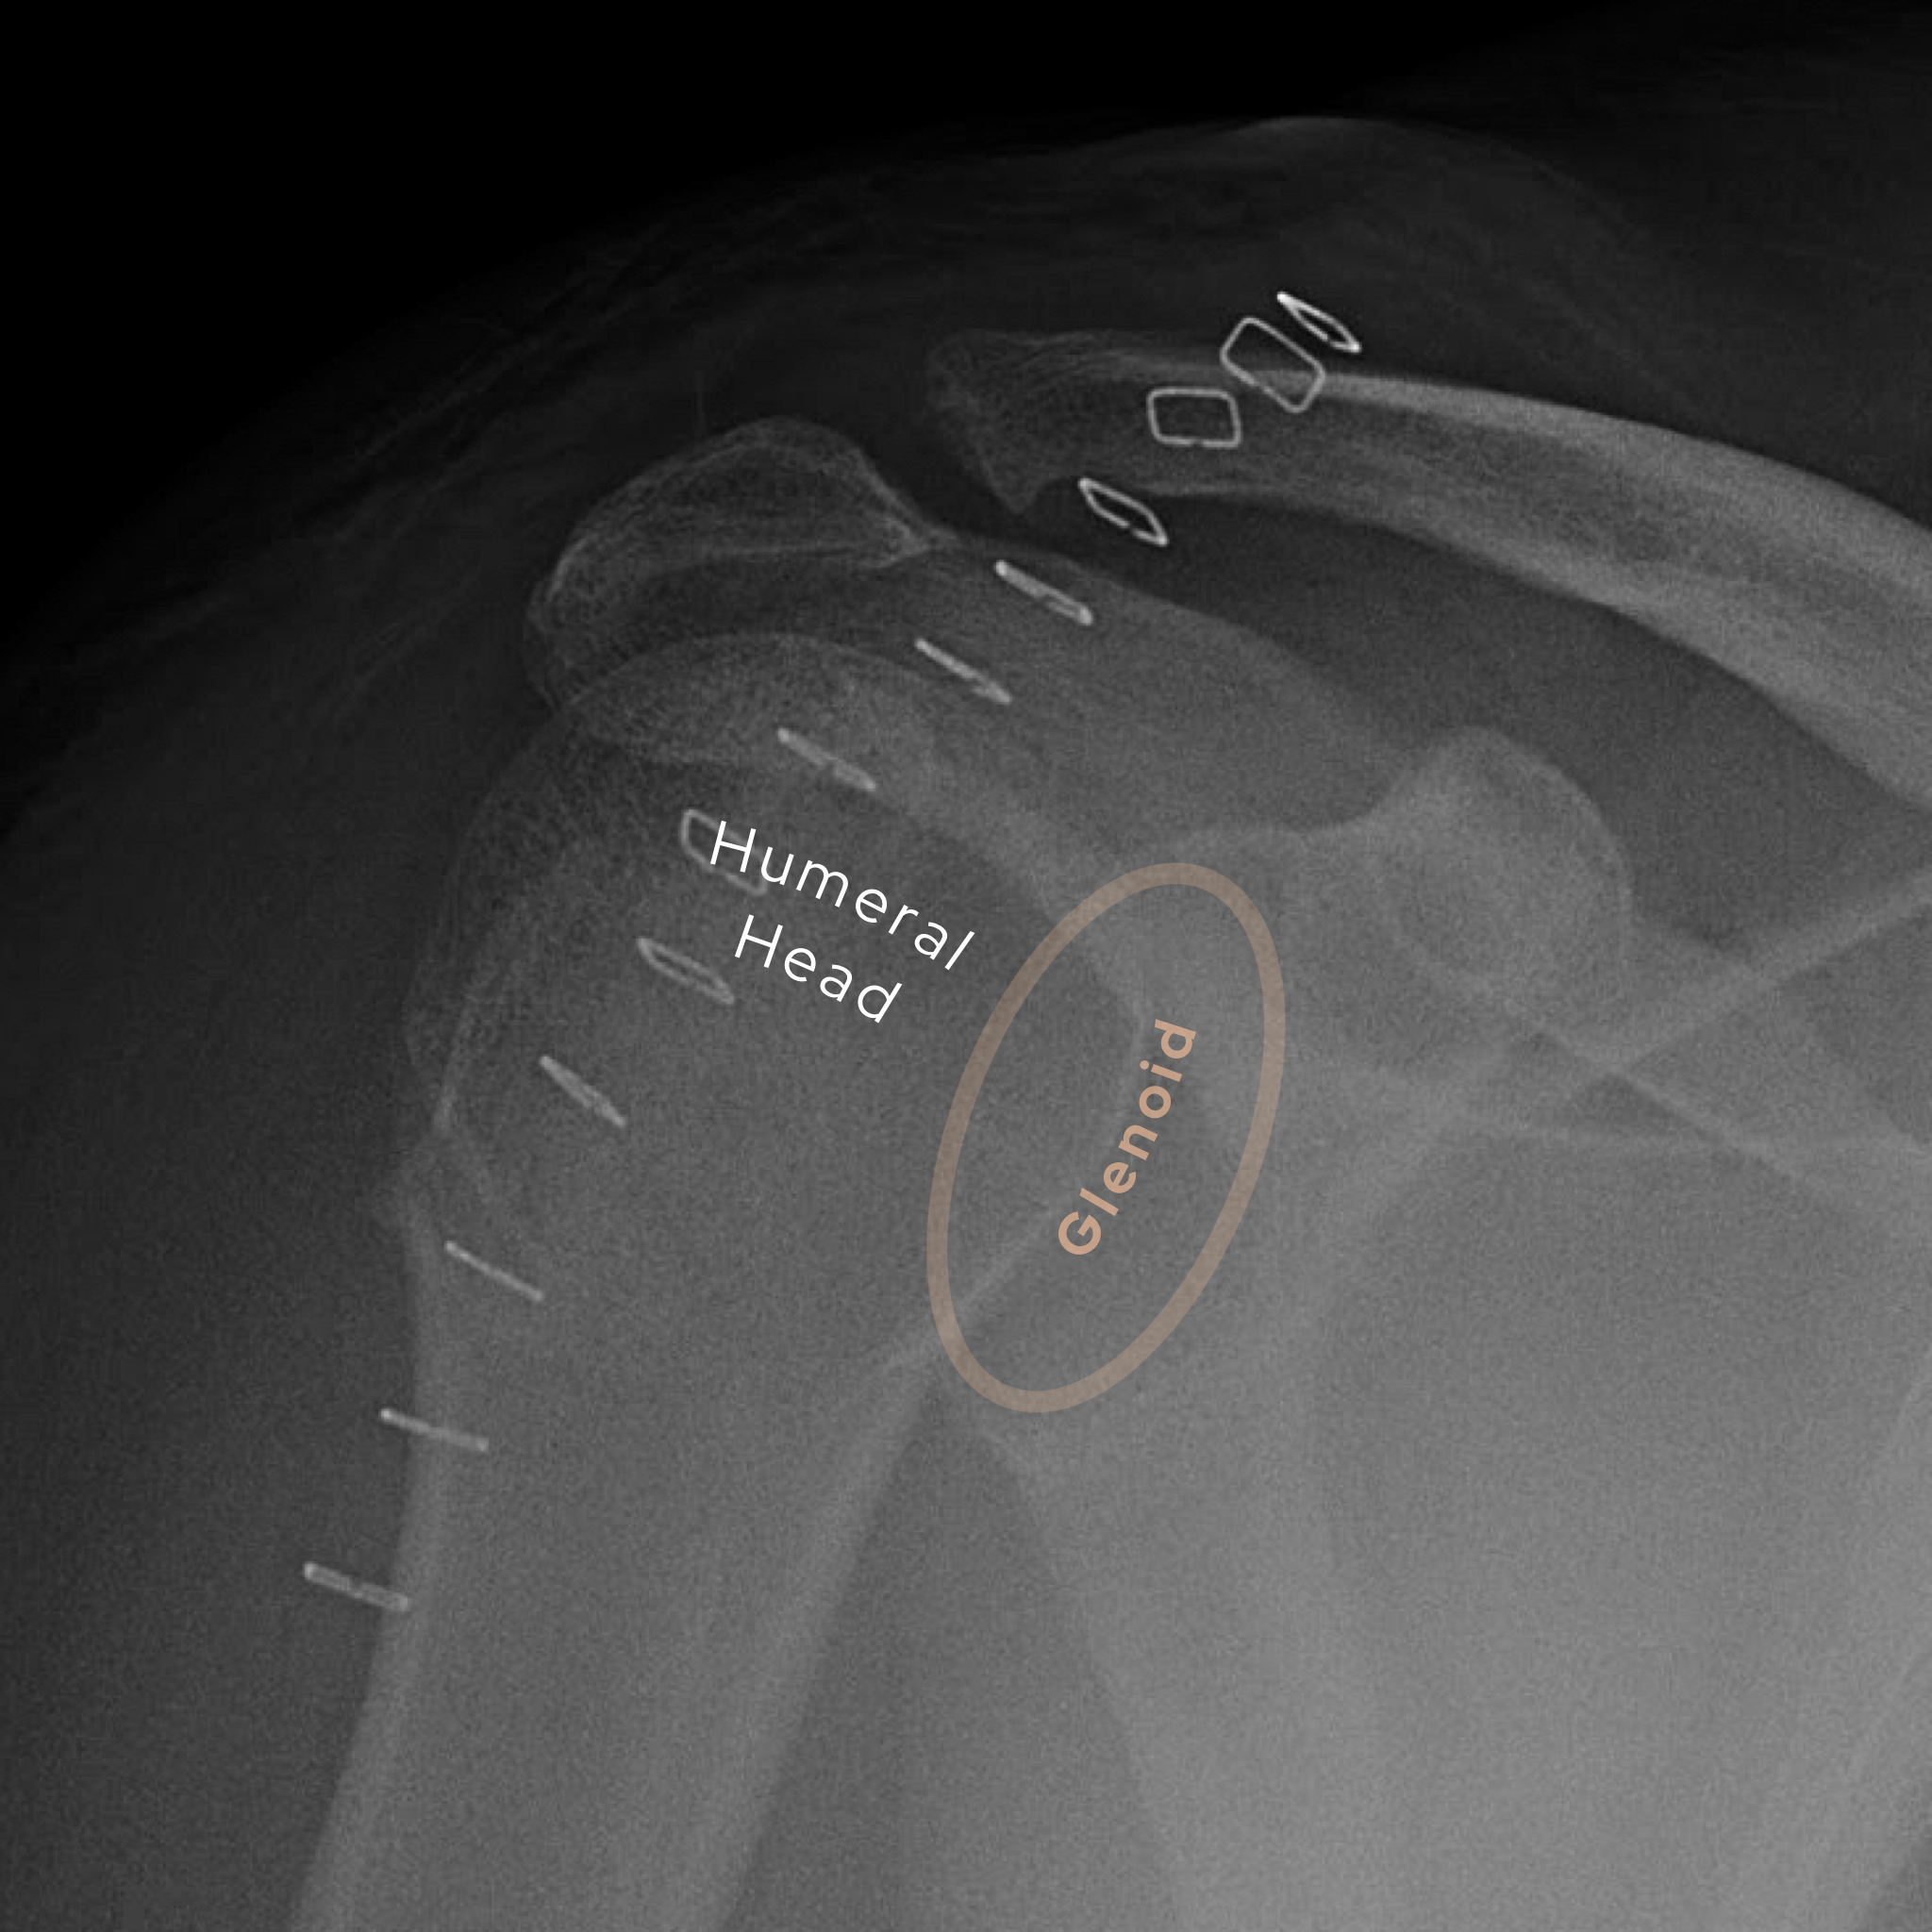

Case 3

A male in his 80s presents to the Emergency Department with shoulder pain and deformity after an episode of trauma. What is the diagnosis?

Choose from one of the following options: